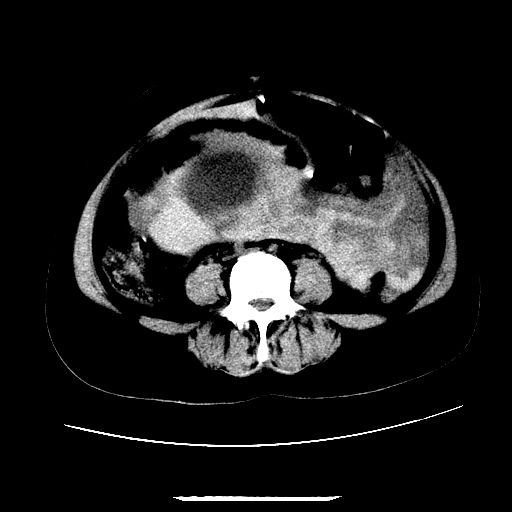

f,45y.怀孕4月晕倒,b超提示死胎,有手术结果,请展开讨论后明天告诉。

膈下-肠间隙内见气体密度影,子宫轮廓显示不清,宫腔-腹腔积液,首选考虑---子宫破裂出血。

1)宫腔妊娠。2)子宫破裂出血,腹腔及盆腔积血。

感谢同行们的高见。手术结果:子宫破裂出血。

我们的诊断是:腹、盆腔积液(考虑腹盆腔脏器破裂出血);宫腔妊娠。让人纳闷的是当时我们没有经验,现在回头看看分析:4月宫腔妊娠:1、洋膜囊不可能紧贴胎体这么小;2仔细看看子宫后壁肌层模糊不清;3腹、盆腔液体来源原因?4、45岁高龄妊娠有晕倒。由此可大胆诊断:宫腔妊娠子宫破裂出血。